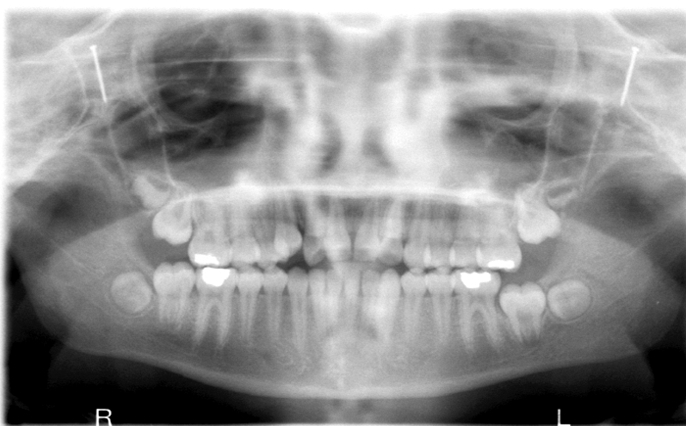

Q

What is wrong with this image?

A

too far forward